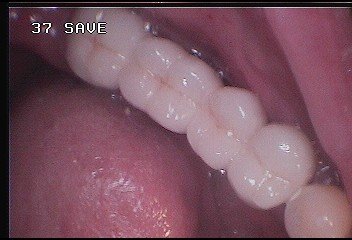

بریج PFM

بریج 4 واحدی PFM-بیمار6